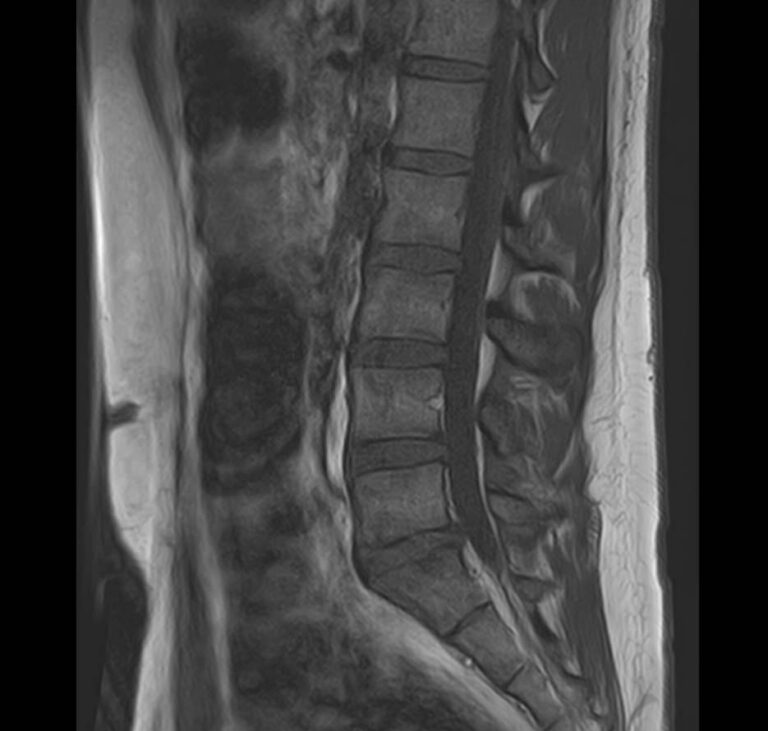

Наиболее точным и эффективным способом диагностики причин появления болей в нижней части спины является МРТ пояснично-крестцового отдела позвоночника. С помощью данного метода можно оценить состояние всех анатомических структур позвоночного столба на исследуемом уровне, безошибочно выявить происхождение болевого синдрома и назначить своевременное лечение.

Многим пациентам интересно, что показывает МРТ пояснично-крестцового отдела. Высокая детальность получаемых с помощью МР-диагностики изображений позволяет с точностью выявить следующие заболевания, локализующиеся в области поясничного отдела позвоночника:

• протрузии и грыжи межпозвонковых дисков;

• дегенеративные заболевания: остеохондроз, спондилез, спондилоартроз;

• последствия перенесенных травм, такие как компрессионные переломы, подвывихи и смещения позвонков;

• новообразования первичного и вторичного генеза;

воспалительные и деструктивные изменения позвонков и окружающих мягких тканей.